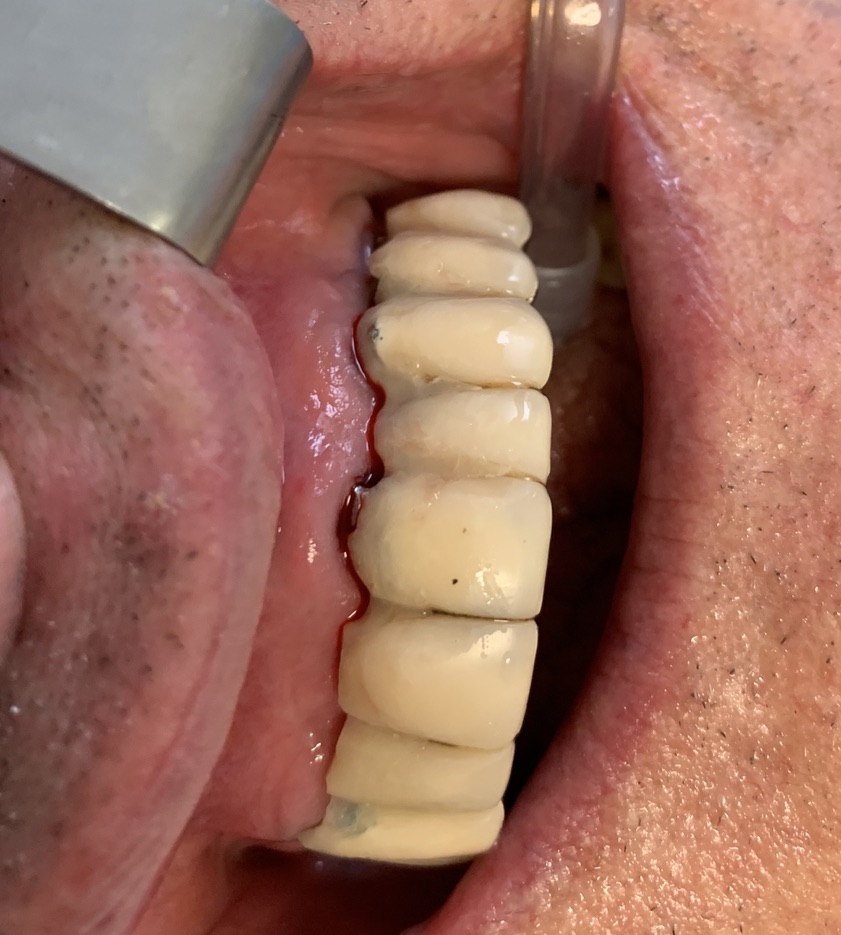

Tipo di impianto: Tramonte     Numero di impianti inseriti: 2     Saldatura: No    Zona dentale: 21   23

App.Rx Endorale:Vix Win     Tac: No     Situazione estrattiva:  impianti postestrattivi immediati   Densità Secondo Misch: D2

Antagonista: fisso/mobile: protesi mobile totale    Spessore mucosa: medio    Altezza di masticazione: media     Bruxismo: no